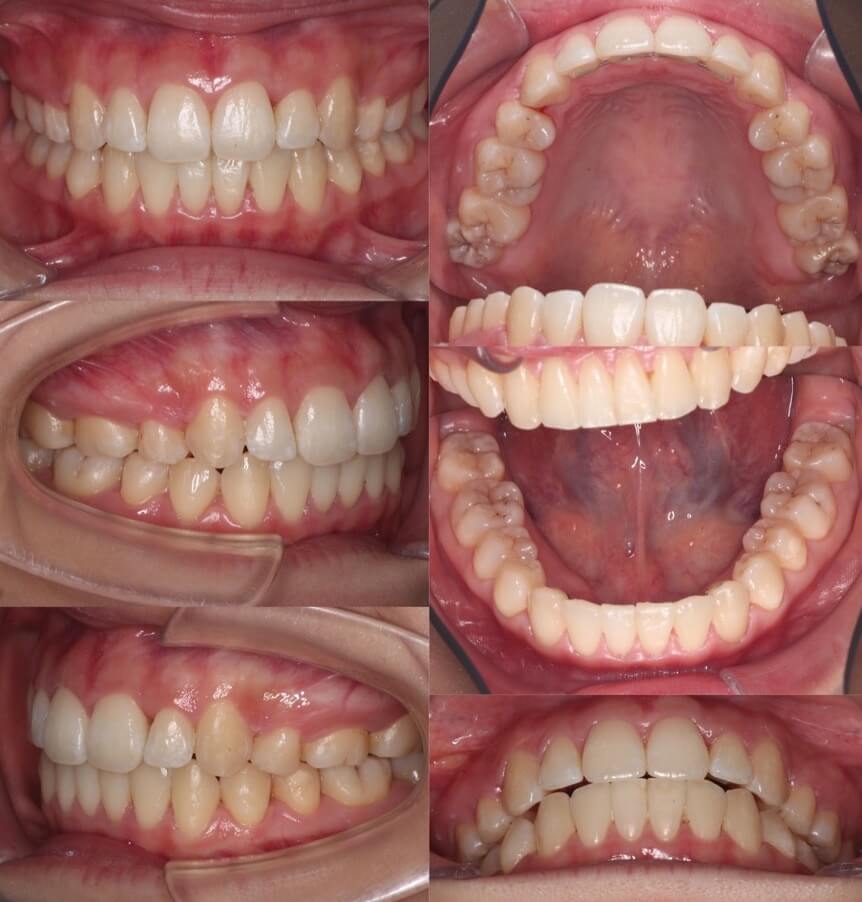

大学生女性・マウスピース型矯正装置・上抜歯

<顔のビフォーアフター>

<症例概要>

主訴:出っ歯

年齢・性別:大学生女性

住まい:千葉県船橋市

症状:上顎前突

治療方針:抜歯空隙閉鎖

治療装置:マウスピース型矯正装置(アライナー装置)

抜歯:上左右第一小臼歯(計2本)

治療期間:2年1か月(1週間交換)

アライナー枚数:61+22ステージ

リテーナー:上下フィックスタイプ+クリアタイプ

治療費用:990,000(税込)

代表的副作用:痛み・治療後の後戻り・歯根吸収・歯髄壊死・歯肉退縮

▶︎その他の副作用

【治療シミュレーション】

上の前歯を少しづつ順番に後ろ入れていく治療方針です。

※マウスピース型カスタムメイド矯正歯科装置は完成物薬機法対象外の矯正装置であり、医薬品副作用被害救済制度の対象とはならない可能性があります。

1cm近く上の前歯が前に出ているケースです。抜歯した隙間に少しづつ前歯を引っ張り、固定源となる奥歯の噛み合わせを崩さないようにして治しました。